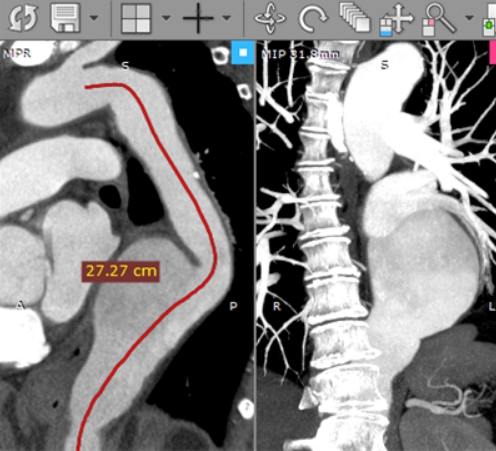

作为专业的医学影像处理平台,RadiAnt DICOM Viewer搭载的智能重建系统是其技术亮点。2D多平面重建模块可生成冠状、矢状及轴向三个标准解剖平面视图,配合动态调节窗口技术,使组织结构和病灶细节在不同灰度对比下清晰呈现。3D体积渲染功能则突破传统二维限制,通过体绘制算法将CT/MRI数据转化为立体模型,支持任意角度旋转观察,为手术方案制定提供可视化支持。

在交互设计方面,软件采用智能标注系统与多点触控技术。测量工具集包含12种专业测量模式,支持实时计算病灶尺寸、角度及体积参数。独创的序列对比功能可同时加载多个影像序列,通过分屏模式实现不同时期检查结果的精准对比,有效提升诊断准确率。